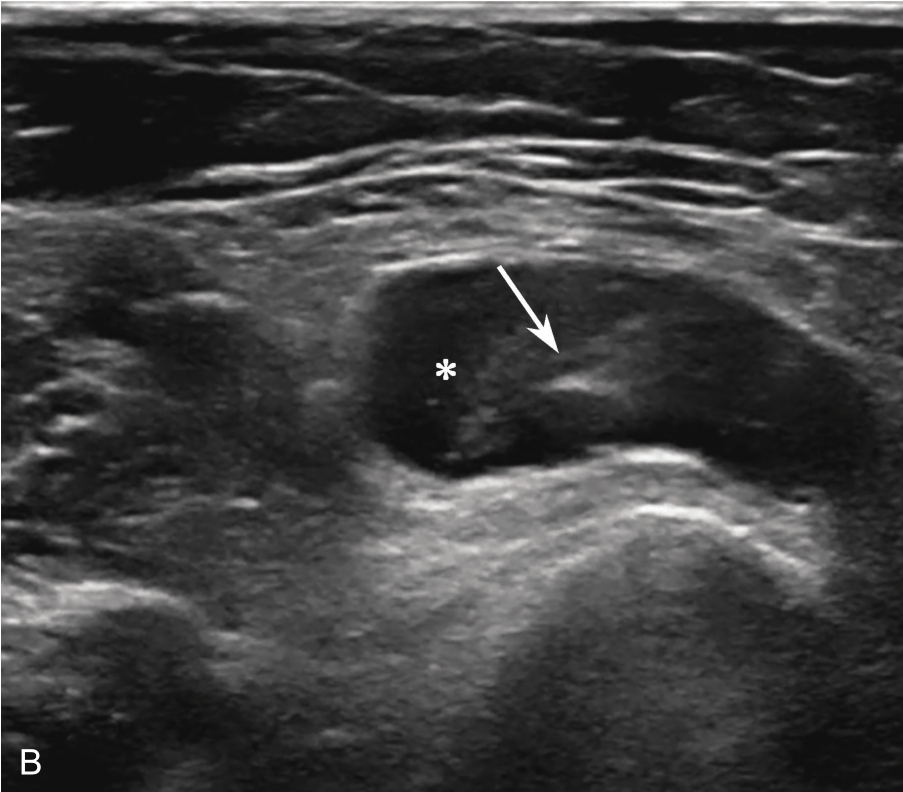

▲ 图2-1-4 超声引导下肩峰下-三角肌下滑囊注射治疗超声图

箭头:穿刺针;星号:滑囊